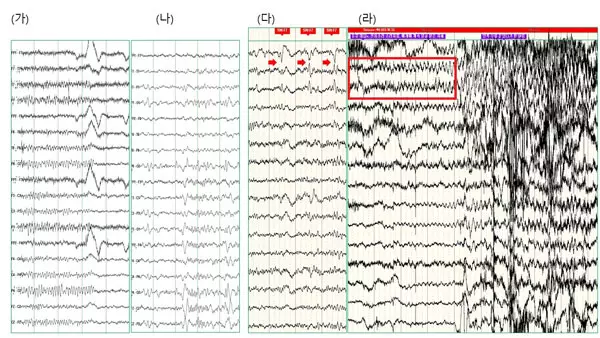

“혈액 검사, 뇌파 검사, MRI 검사 등 세 가지 검사를 진행한다. 혈액 검사는 면역 기능을 포함한 건강 상태를 파악하기 위해, 뇌파 검사는 뇌의 전기적 이상을 보기 위해 시행한다. 특히 발작 당시 뇌파의 양상을 확인하는 게 굉장히 중요하다. MRI는 뇌의 구조를 보는 거다. 미세병변까지 자세히 확인하려면 일반 MRI보다 해상도가 높은 MRI 검사를 진행해야 한다. 다만, 아직 뇌 MRI만으로 모든 원인을 찾을 수는 없다.”